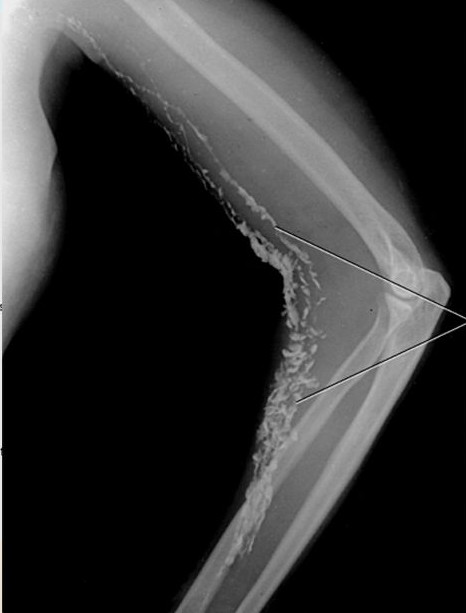

- лимфография – в лимфатическую систему вводят контрастное вещество, делают рентгенологические снимки, по ним оценивают состояние лимфатических сосудов – в частности, определяют участки застоя лимфы и оценивают скорость ее движения;